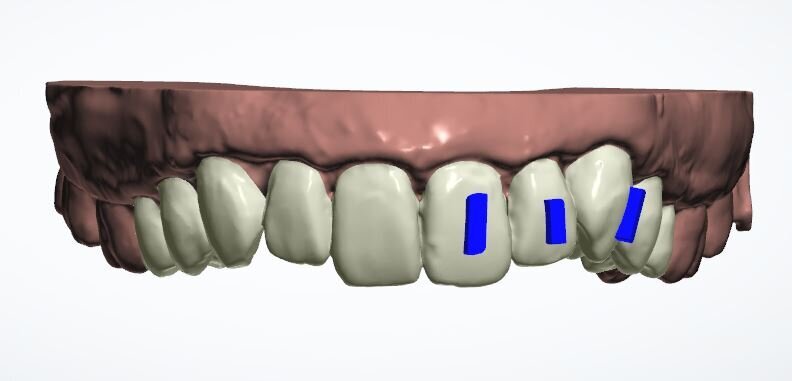

Fig. 13a: Current position

Fig. 13b: Three refinement aligners

Fig. 13c: Six refinement aligners

At the end of the 18 planned aligners, there was still a central diastema of approximately 0.2 mm and tooth #23 had not rotated completely. The laboratory offered three (free) or six (for a fee) refinement aligners. The patient chose the latter, reasoning that as we had come this far, we should finish properly. He was charged the laboratory cost only.

As the refinement aligners were progressing, I took impressions for whitening trays, and the patient wore 16% carbamide peroxide gel for three weeks between wearing his aligners. By the end, the diastema had closed and tooth #23 had improved a little but not entirely. However, the patient declared himself happy and elected for Essix retainers over a fixed wire, as he liked the idea of being able to floss all of his teeth, plus he was so used to wearing aligners that wearing retainers at night posed no problem.

The IAS support forum helped me a great deal in my first case. When I was concerned about the midline diastema and the uprighting of tooth #23, I was advised by Dr Qureshi to obtain a leaf gauge, which I did, and I cannot now imagine working without it. Dr Perez also helped me to understand that the anterior–posterior relationship was working against this case in uprighting tooth #23 completely. The mandibular teeth would have required aligning for this to be possible and now that I am more experienced I feel I could spot this from the beginning.